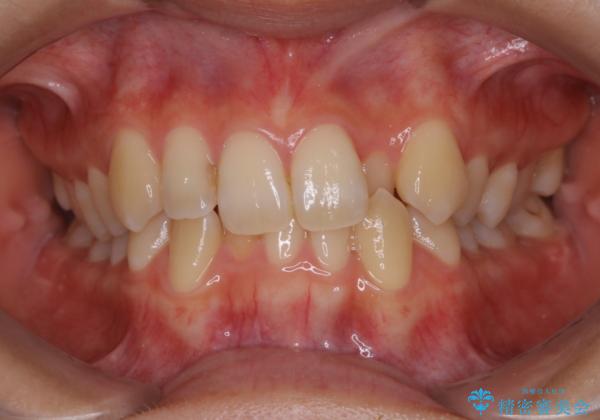

下顎前歯の先天欠損と上顎前歯のクロスバイト:インビザライン治療

- 上の前歯が1本後ろに入ってしまっていることが気になるとご相談にいらした方です。

元々下の前歯が1本欠損しており、上下の噛み合わせや、歯のサイズバランスを考慮しながら治療を行いました。

クロスバイトしている歯が深く噛み込んでおり、この歯を外に出してくる際に強い咬合力が加わると歯が失活する恐れがあることを説明し、合わせて咬筋へのボトックス注入を行いました。

下顎切歯が1本欠損しているため、上顎前歯部を少しずつストリッピングして、上下の噛み合わせ、バランスの向上を図りました。